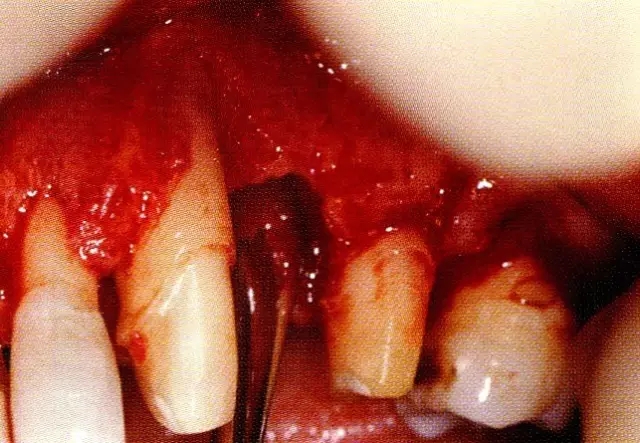

▲圖7-1  左下6近中可觀察到3壁性垂直性骨缺損。此病例考慮到齦瓣供血關(guān)系,在前磨牙部位進行了減張切開,沒有進行縱切開。并利用刮治器、牙周外科用車針進行了徹底的骨缺損部位搔刮。